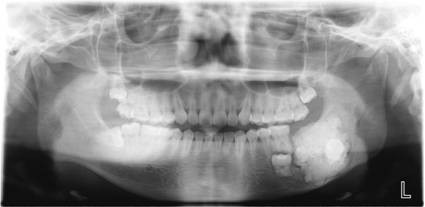

数字化口腔曲面体层片